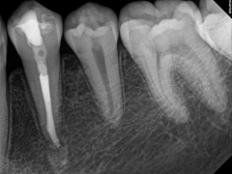

Every tooth has different numbers of roots and canal systems. With the help of magnification and high tech equipment, Dr. Jung can locate and treat the canals including MB2 on upper molars and MM on lower molars.

Apexification

In this case, the unhealthy pulp is removed. The MTA will be placed into the apical portion of the root to stimulate hard tissue to form near the root tip (approximately 4-5 mm's of MTA condensed carefully into the apical portion of the root). The coronal portion of the canal space is then filled with restorations to re-enforce the root and provide more structural integrity. The patient is recalled periodically to monitor the progress of the root-end closure, and decide whether other measures, like root end surgery, may be required.